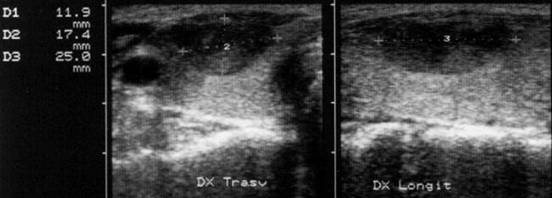

Femeie 32 ani. Nodul unic la apexul lobului drept, contur net, hipoecogen, nu influienteaza parenchimul din jur, neomogen cu arii hiperecogene si hipoecogene, de 12x17x25mm, (2,6 cc).

Citoaspiratia: leziuni foliculare.

Examen histologic postoperator: adenom microfolicular cu aspect trabecular.

ecocolordoppler si powerdoppler- acelasi nodul

Vascularizatie interna, mai evidenta in powerdoppler.